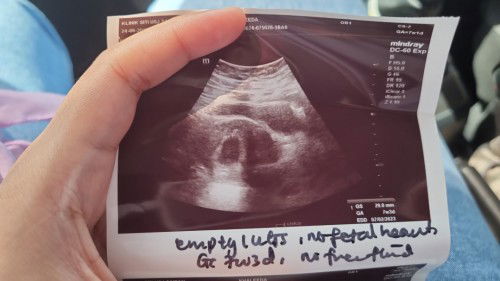

Hi mommies nk tny ada sesiapa tahu tk klinik yg okay utk scan baby area shah alam or subang jaya? Sbb masa 7weeks saya pegi klinik siti utk buka buku bila doktor scan hanya ada kantung sahaja, tk ada hearbeat so doktor refer saya ke hospital tpi bila bgitau mak dan mak mertua diaorg x bgi saya pegi katanya takut dri tk gugur nnti gugur. Saya xde bleeding or apa2 skrg saya dh 9weeks jumaat nnti bru nk gi kk buka buku pink. #firstmom #pleasehelp